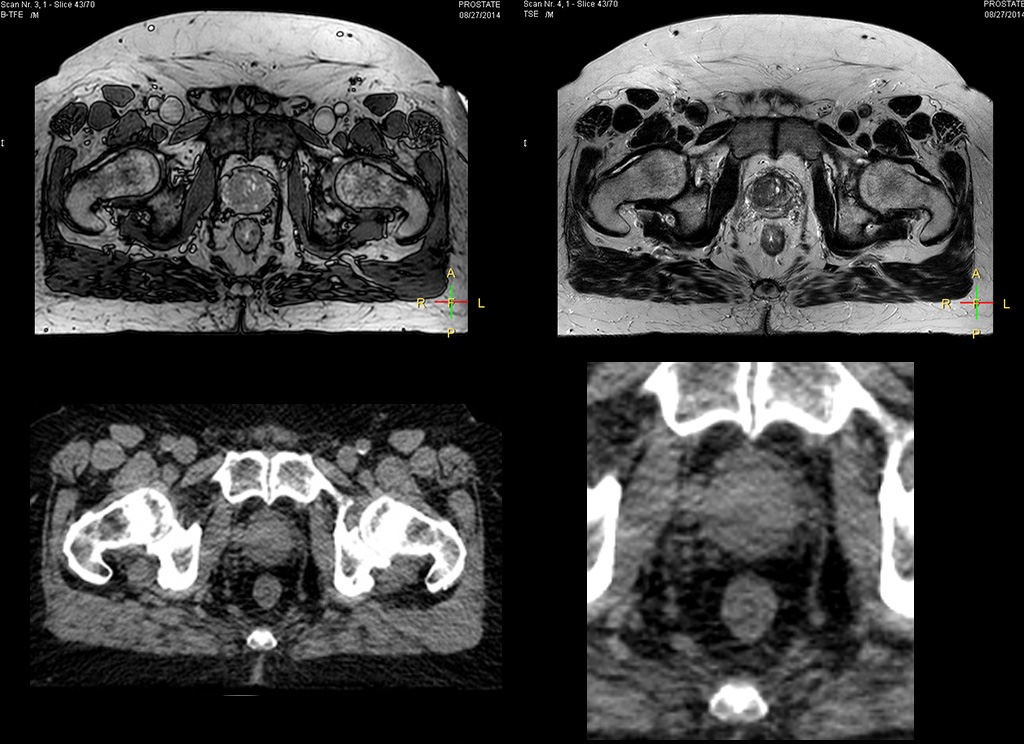

“The biggest problem for CT-based planning, especially in prostate, is you can’t see the cancer very well,” says Dr. Stevens. “On CT it can be quite challenging to see the edge of the prostate especially at the apex. When the edge of the prostate can’t be delineated well on CT, radiation oncologists will increase their margins a little bit so they don’t miss it, but that can also increase toxicity.” “Using MR, the prostate is well delineated. We quickly see the edges of cancerous tumors like in prostate cancer, and as normal structures can be defined, we can optimize the treatment plan to protect these organs and their normal function. This can potentially improve the outcome. And it improves workflow as well. We can contour more quickly, confident that the tumor is going to be in the field.” “The Ingenia 3.0T MR scanner provides high resolution allowing us to make scans fast for the patients. It also gives the potential to include methods like MR spectroscopy and diffusion weighted Imaging, which we’re in the process of doing right now,” Dr. Stevens adds.

Beaumont Health System (Royal Oak, Michigan, USA) is one of the largest health systems in the USA, with eight hospitals and 153 outpatient sites, a medical school and a research institute. The Radiation Oncology (RO) department houses a dedicated Ingenia MR-RT solution that is routinely used for clinical and research MR-RT activities. “The main reason to integrate MR imaging in RT planning is the superb soft tissue contrast that allows detailed delineation of tumors and healthy organs, which is crucial for RT planning,” says Craig W. Stevens MD, PhD. “MR also provides information on functional and biological activities in tumors, background tissue and normal organs, which may also be used in RT planning,” says physicist Di Yan, DSc, FAAPM.” “We currently use MR-RT mainly in the abdomen and pelvis region: prostate, colorectal, pancreatic, cervical, and liver. Also in the brain, we are starting to use it,” says Dr. Yan.

“When a patient registers, first CT simulation and MR simulation are done, followed by CT-MR registration on Pinnacle3. Then the target and normal organ delineation is performed on MR images. Meanwhile we create a reference CT image for online treatment and localization correction. During the treatment phase we can perform additional MRI scans to visualize the anatomy changes and create an adaptive plan. This plan basically adapts the treatment plan to the changes.” “Along with its great benefits, MR has introduced some new challenges,” Dr. Stevens says. “Radiation therapy teams generally have no experience with MR. The Philips training helped us to implement fully the things we can do with the Ingenia MR-RT system. So the training, as well as having a good MR physicist, is critical.”